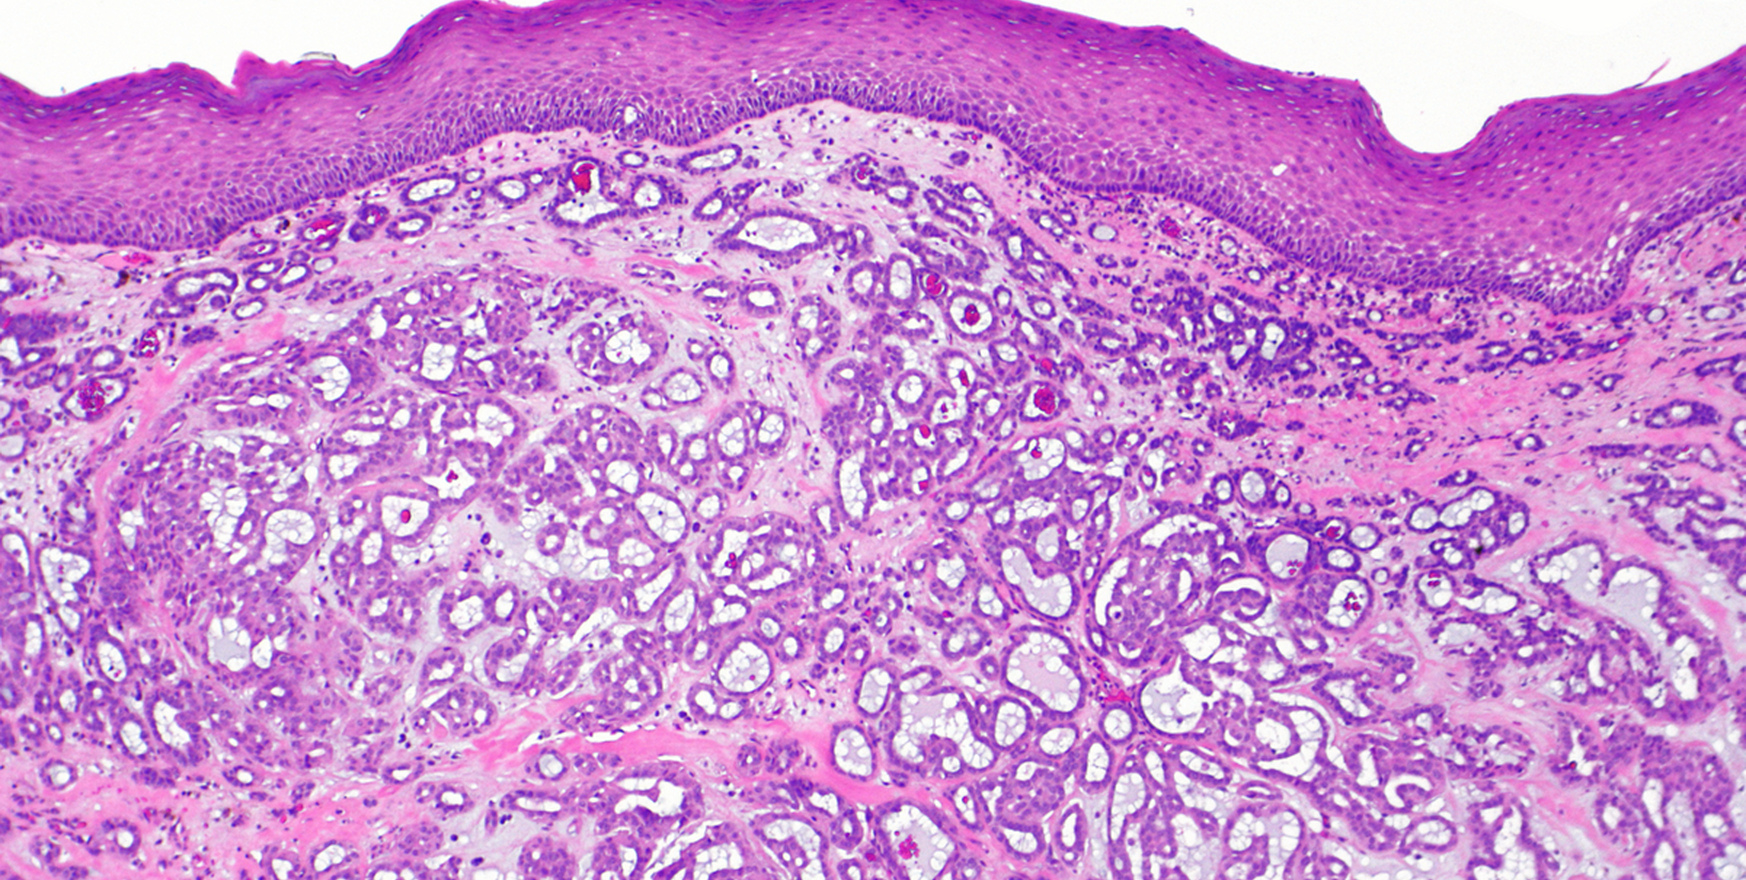

- Биопсия. Для подтверждения диагноза и исключения онкологических изменений врач может взять образец ткани (биопсию) с поражённого участка для гистологического исследования.